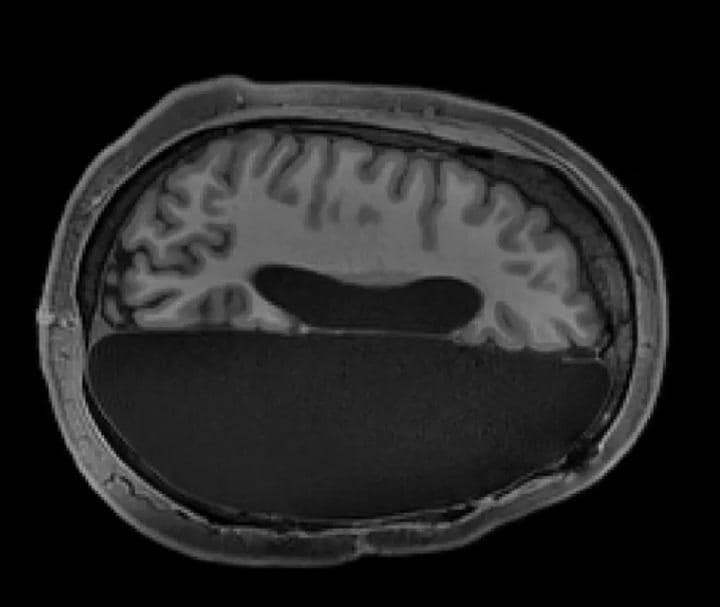

「コンピューターの前で、脳が半分しかないMRI画像を見ても、今さっき話をしたり歩いたりしていた人たちのものとは信じられなかった」

研究チームは6人の協力者のMRI画像を健康な6人の画像と比較。さらに一般人1500人の脳データとも比較した。